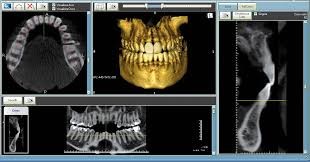

DENTAL STUDIO SOFTWARE 3D CAPABILITIES

The advanced technology of the Rotograph Evo 3D allows to see the images on the workstation in real time, while the machine is rotating. Simultaneously, the 3D reconstruction module creates the volume using a specific algorithm for artefact reduction. Once the volume reconstruction is completed, the 3D visualization module shows the entire dental status on a single view, thus giving a great support on the study of the single specific case. The representation of the windows is loaded automatically during the first acquisition and it's then fully customizable by the user. Once the image is obtained, the Dental Studio imaging Software makes then available to the user all our expertise in terms of image treatment and specific 3D planning.